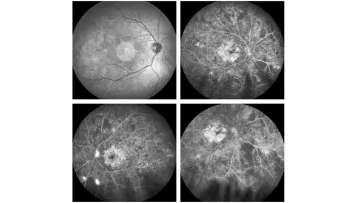

Neue Gentherapie gegen Netzhauterkrankung

Am Universitätsspital Basel wurde einem fast erblindeten 52-Jährigen ein Gen unter die Netzhaut eingesetzt, damit dieser wieder besser sehen kann. Der Mann aus Zug leidet unter einer Retinitis pigmentosa und soll mithilfe der Therapie wieder besser sehen können.